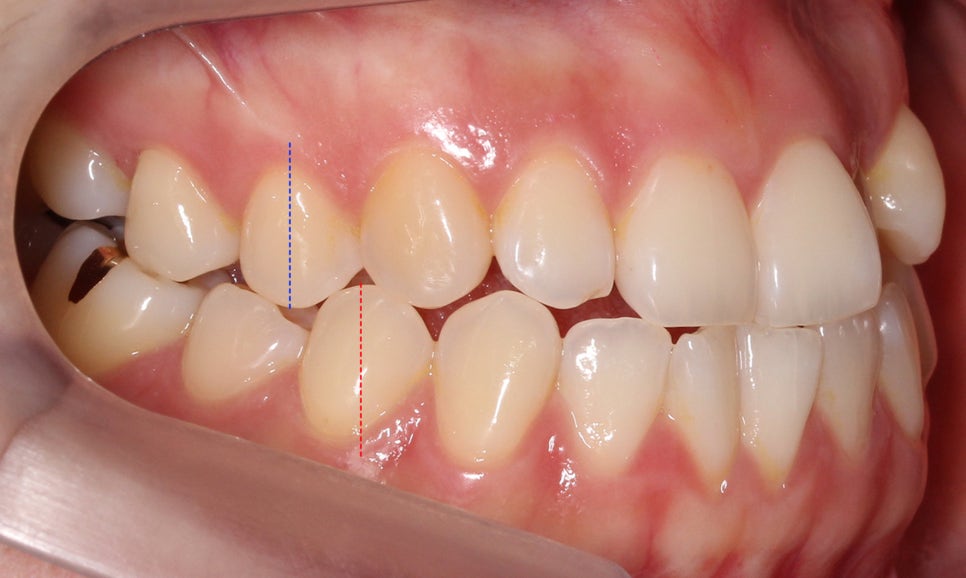

전체교정 후

절단교합 교정 후 정면 구내 사진입니다.

상악과 하악 모두 최후방의 사랑니를 발치하여

치아가 배열될 수 있는 공간을 확보하였는데요,

전치부의 교합을 바로잡고 구치부 부정교합을

바른 교합 상태로 만들기 위해서 경우에 따라

사랑니가 아닌 소구치를 발치해야 할 수 있기 때문에

치아교정 전 반드시 교정전문의와 상담이 필요합니다.

교합평면도 좌우 모두 클리피씨 교정 후

어금니의 교합이 바르게 교정된 모습입니다.